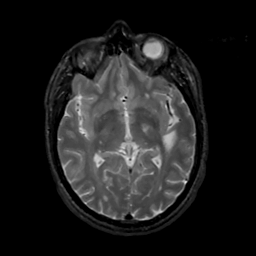

MR Study #4, March 3, 1991 -- Slice #24

[Home][Help][Clinical][Tour 1][Tour 2] Slice 24